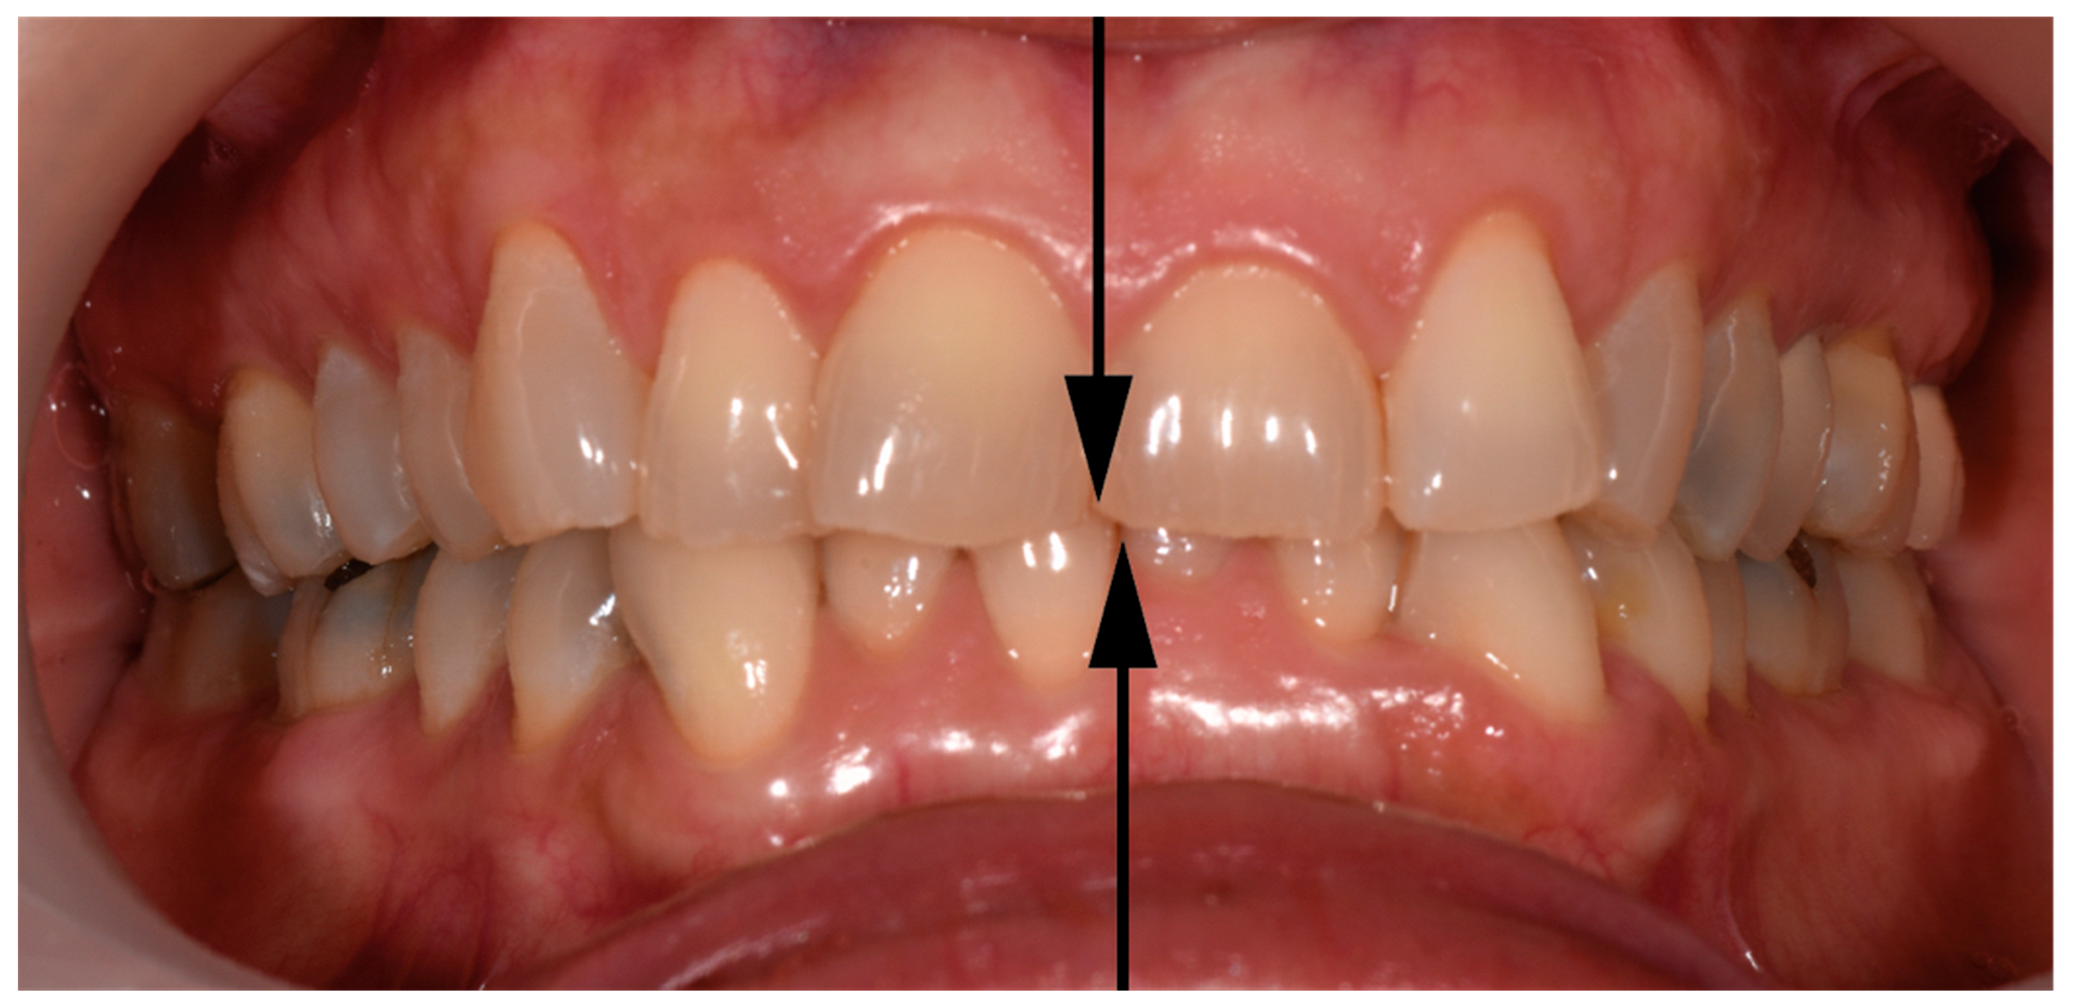

| Side toward lower dental midline shift was deviated—no. (%) | |

| Right | 16 (42.1) |

| Left | 13 (34.2) |

| Both | 8 (21.1) |

| Cannot be assessed | 1 (2.6) |